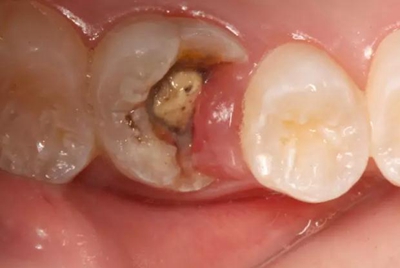

病例一 女性,20歲,大學(xué)生,要求補(bǔ)牙,檢查口內(nèi)可見A6大面積缺損,近中牙齦息肉,拍X片,根管充填物略差,但根周未見明顯陰影,口內(nèi)檢查無(wú)叩痛。建議患者冠延長(zhǎng)手術(shù)+高嵌體修復(fù)。

患牙遠(yuǎn)中邊緣嵴完整,強(qiáng)度沒(méi)有降低,故擬保留遠(yuǎn)中邊緣嵴,高嵌體修復(fù)。首先去除腐質(zhì)及原墊底材料,流體樹脂+3M Z350XT樹脂墊底。局麻下行冠延長(zhǎng)手術(shù)。在此需要提及個(gè)人的一個(gè)觀點(diǎn)。冠延長(zhǎng)手術(shù)原則上要求3-6個(gè)月以上才能永久修復(fù)。但是個(gè)人喜歡后牙肩臺(tái)建立在齦上,所以修復(fù)后的修復(fù)體邊緣位于牙齦上方1mm,對(duì)牙周的愈合影響較?。ㄈ绻麨辇l下邊緣則要慎重),故該患者術(shù)中按照齦上邊緣的設(shè)計(jì)進(jìn)行冠延長(zhǎng)手術(shù)。以下為術(shù)中: